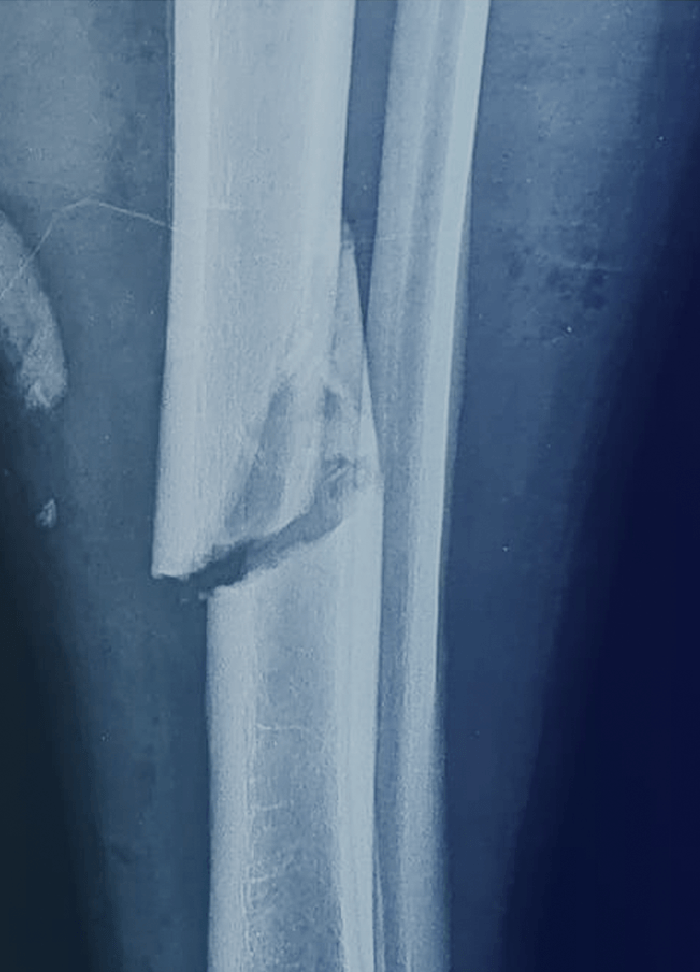

Lesiones internas o externas provocadas por la acción de agentes físicos o mecánicos exteriores.